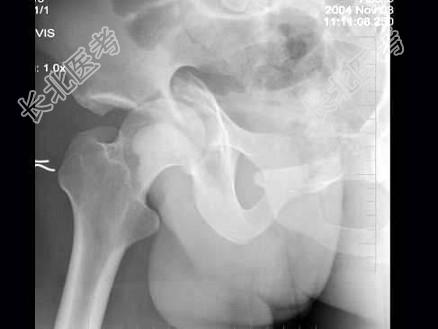

- 单项选择题男,32岁, 因车祸致右髋关节肿痛,活动受限摄片如图示, 最可能的诊断是 ( )

A、骨盆Ⅰ型骨折

B、骨盆Ⅱ型骨折

C、骨盆Ⅲ型骨折

D、骨盆Ⅳ型骨折

E、以上均不是